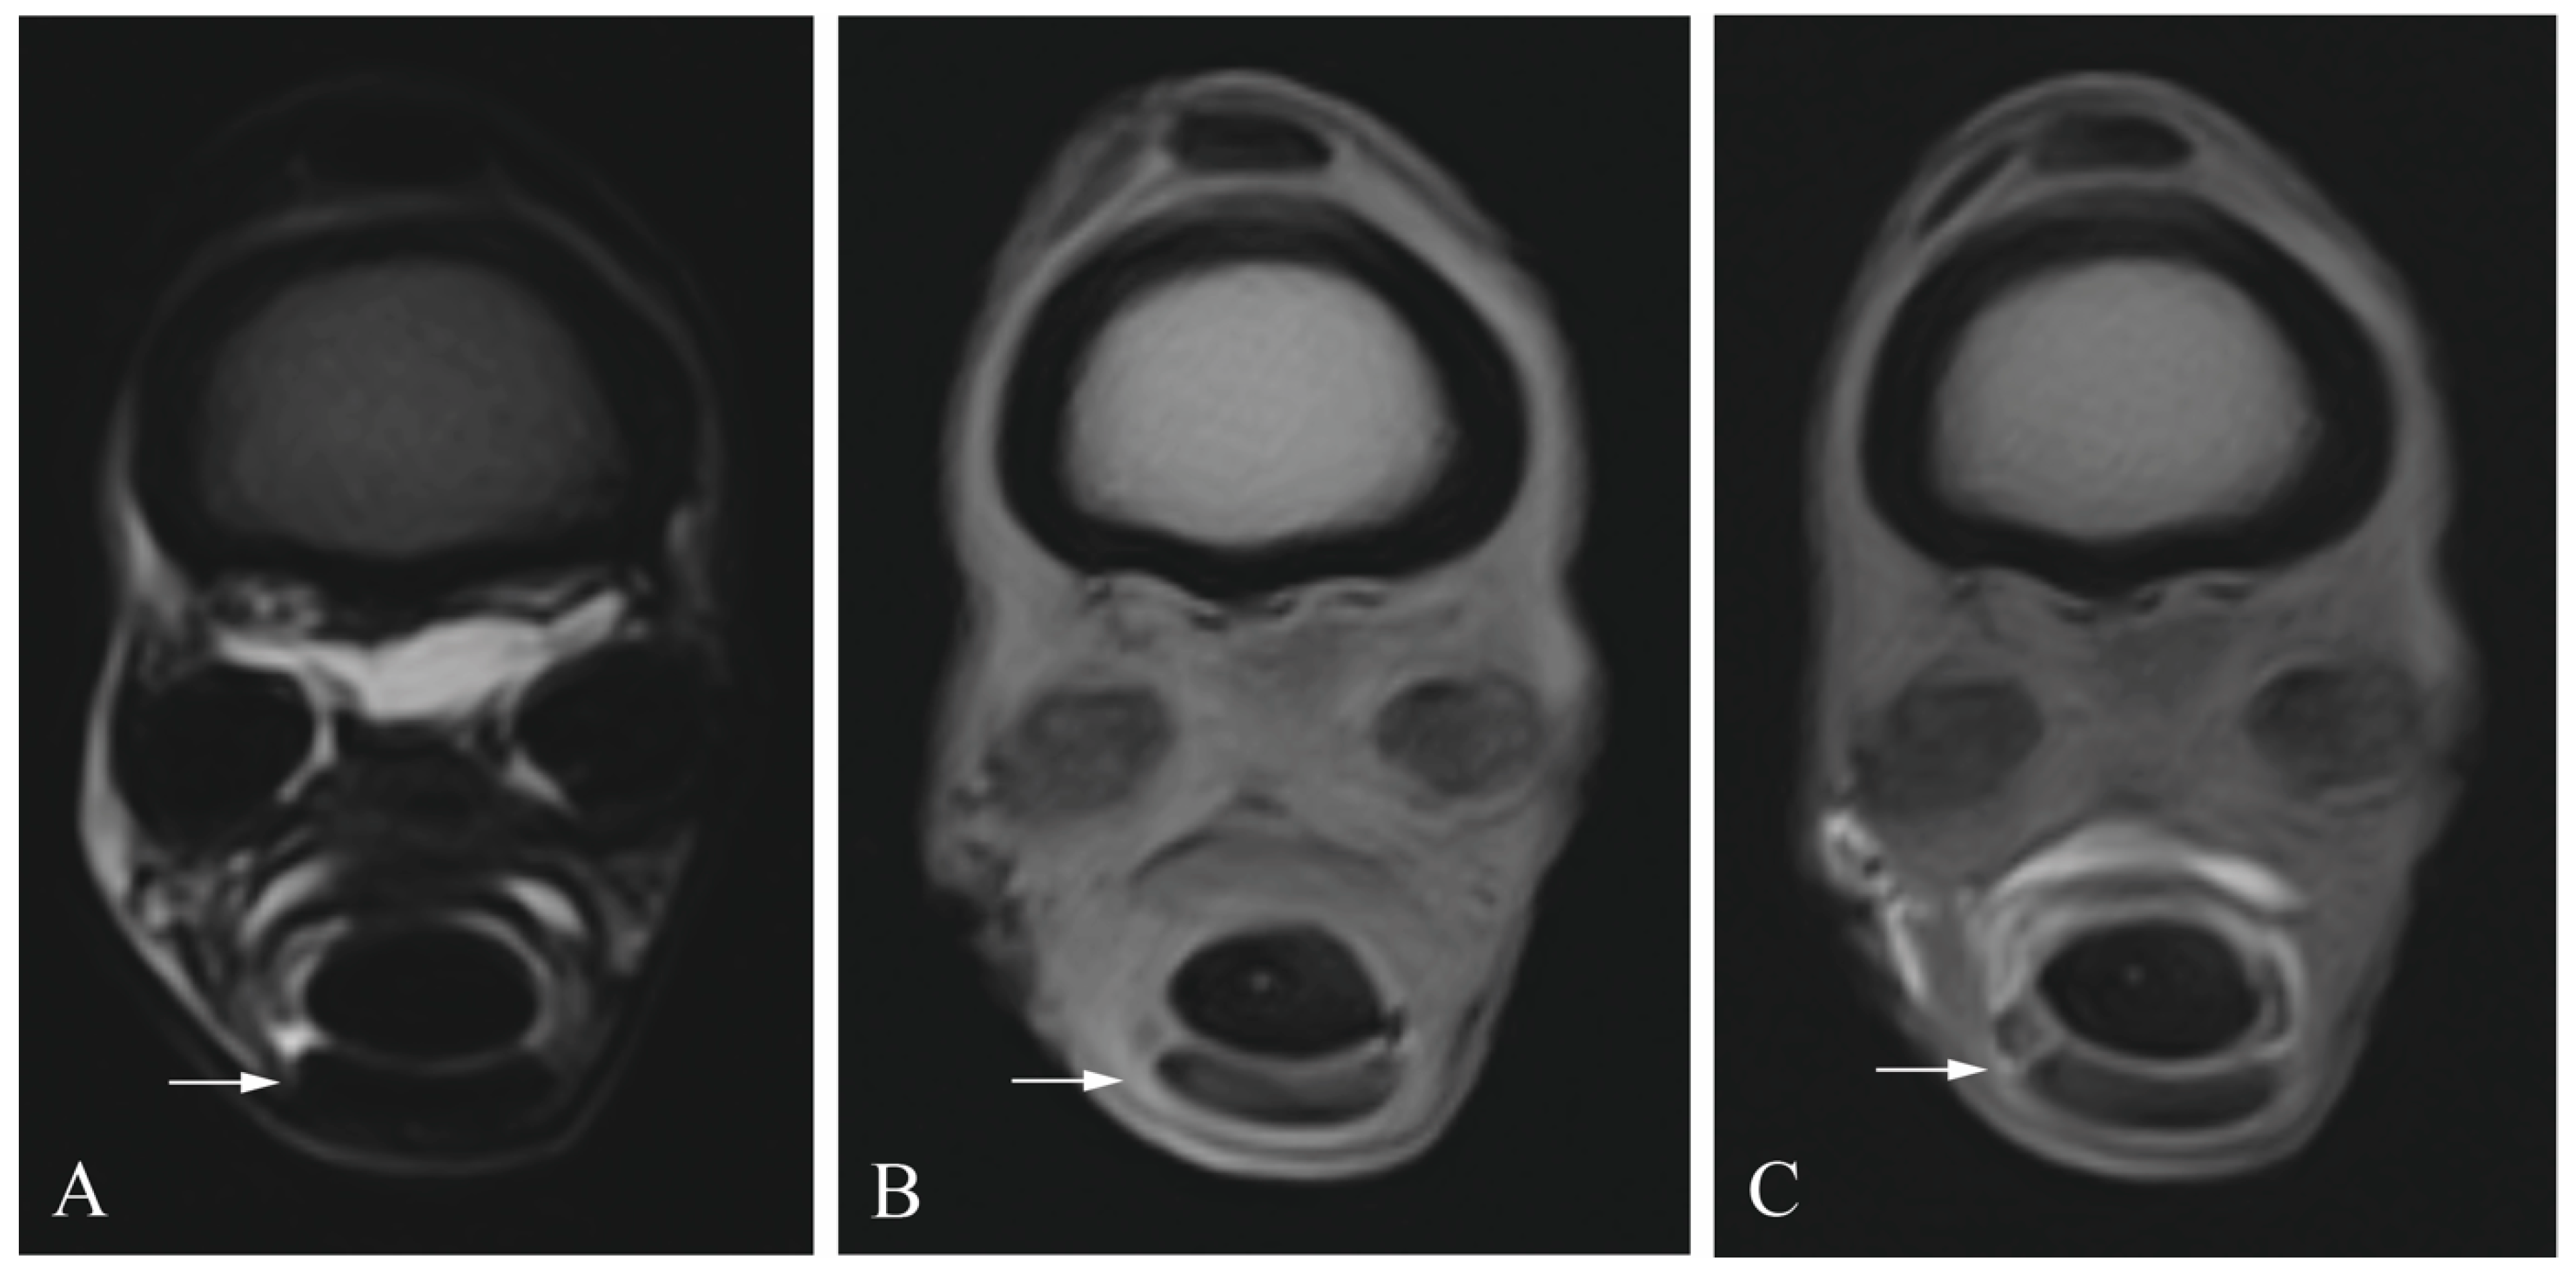

2.2. Tenoscopic Procedure

2.3. Diagnostic Imaging

2.4. Image Analysis